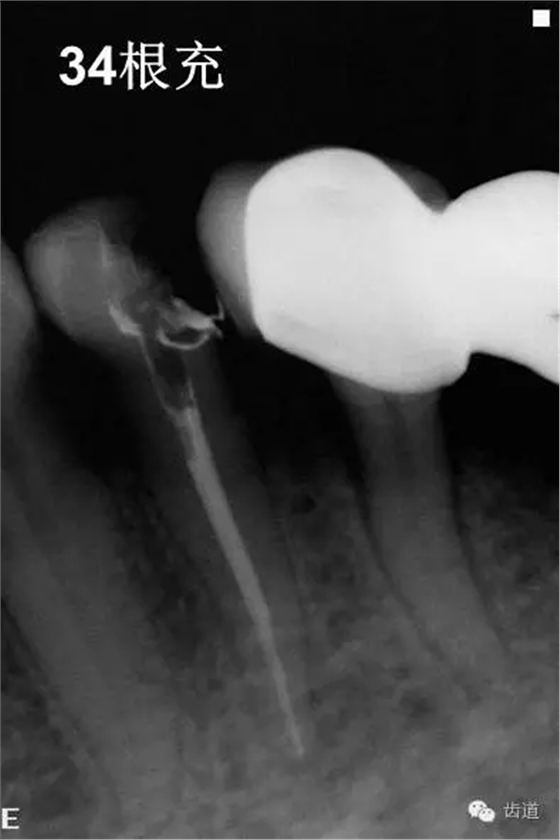

4、34常規(guī)根管治療。(2013年8月)

5、34冠修復(fù),45,46聯(lián)冠修復(fù)(2013年10月)